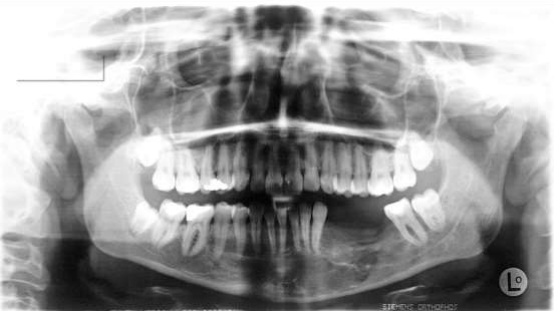

Fig 2: September 1993:  suspected recurrence regio 36-43: enucleation, anterograde root tip resection front lower jaw, filling with AAA-Bone: histology: desmoplastic fibroma

Figure 2